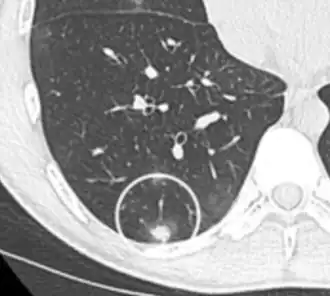

A lung nodule or pulmonary nodule is a relatively small focal density in the lung. A solitary pulmonary nodule (SPN) or coin lesion,[1] is a mass in the lung smaller than three centimeters in diameter. A pulmonary micronodule has a diameter of less than three millimetres.[2] There may also be multiple nodules.

One or more lung nodules can be an incidental finding found in up to 0.2% of chest X-rays[3] and around 1% of CT scans.[4]

The nodule most commonly represents a benign tumor such as a granuloma or hamartoma, but in around 20% of cases it represents a malignant cancer,[4] especially in older adults and smokers. Conversely, 10 to 20% of patients with lung cancer are diagnosed in this way.[4] If the patient has a history of smoking or the nodule is growing, the possibility of cancer may need to be excluded through further radiological studies and interventions, possibly including surgical resection. The prognosis depends on the underlying condition.